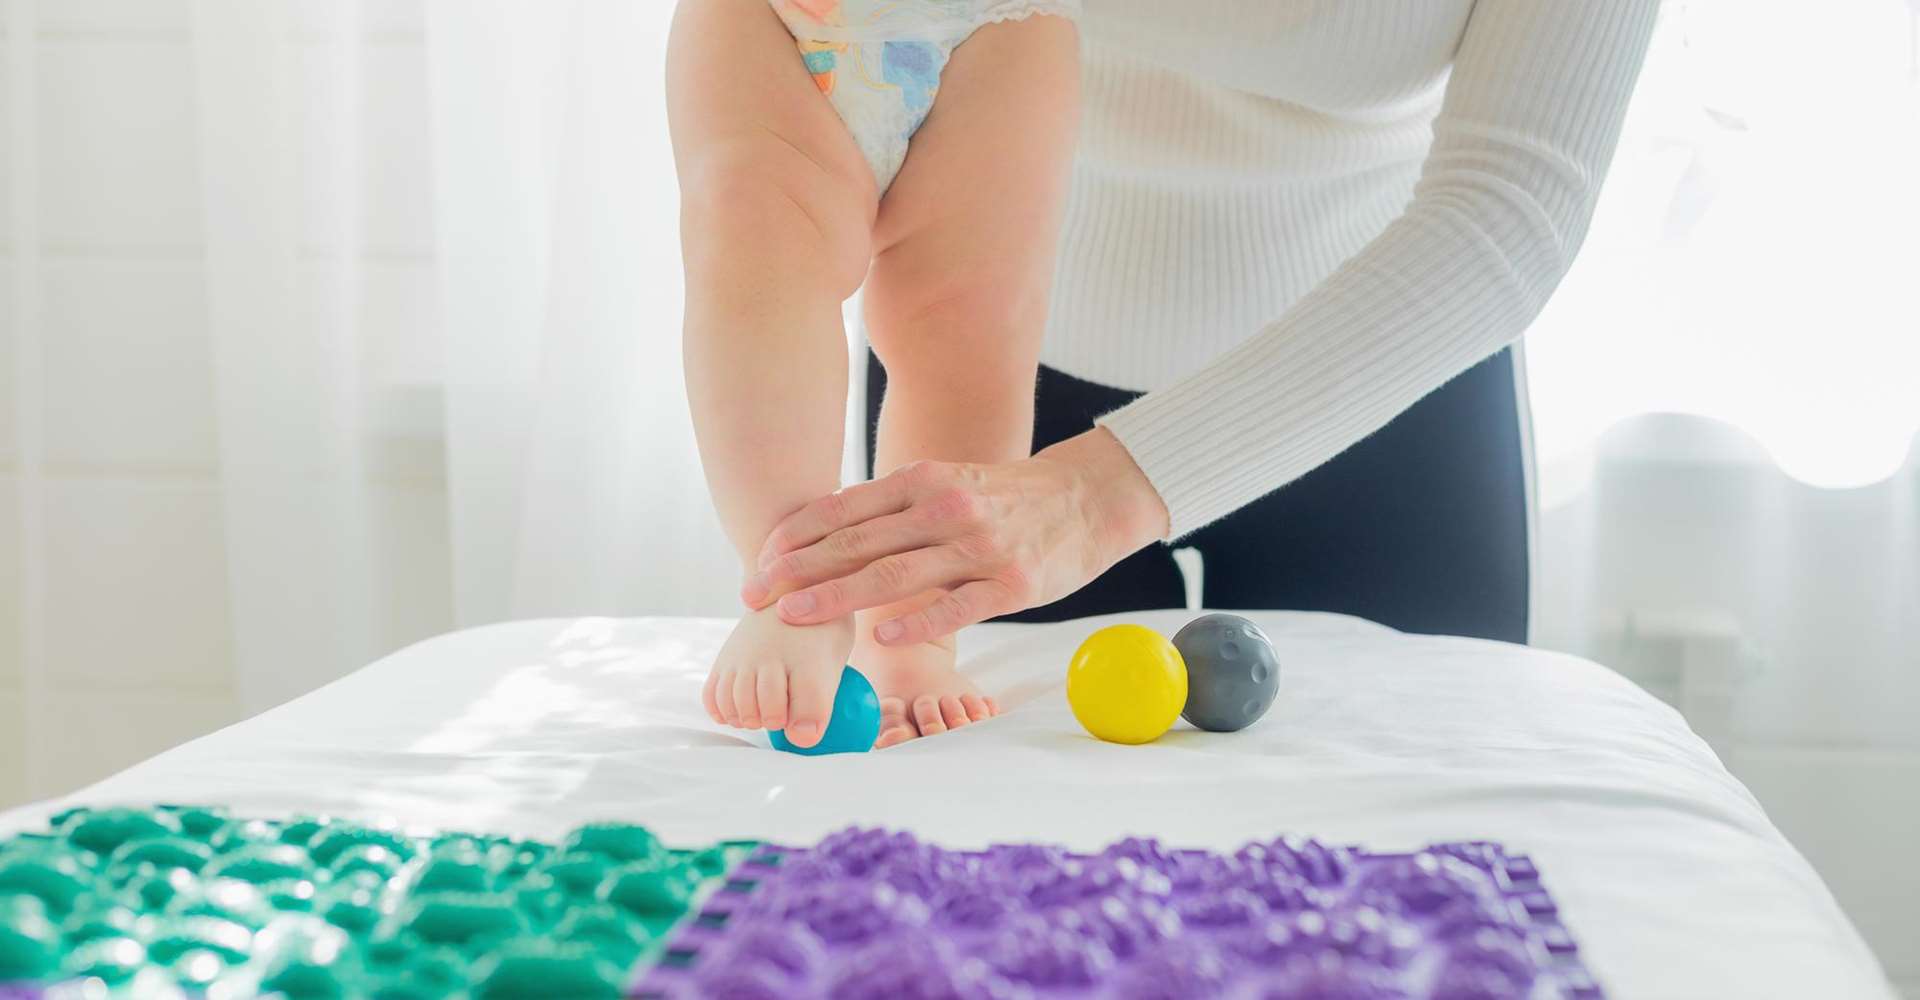

مرکز تحقیقات توانبخشی اعصاب اطفال در سال ۱۳۸۰ در دانشگاه علوم توانبخشی و سلامت اجتماعی شروع به کار نمود و درسال 1387 موفق به دریافت موافقت اصولی گردید. این مرکز در حال حاضر دارای پنج نفر عضو هیات علمی تمام وقت و 15 نفر محقق پاره وقت و 2 نفر محقق افتخاری می باشد. رسالت مرکز انجام پژوهش و تولید علم در راستای یک هدف غایی و رسالت ملی، یعنی ارتقای سطح تکامل همه جانبه کودکان ایرانی، و مداخله به هنگام و توانبخشی زودهنگام در اختلالات تکاملی کودکان است.